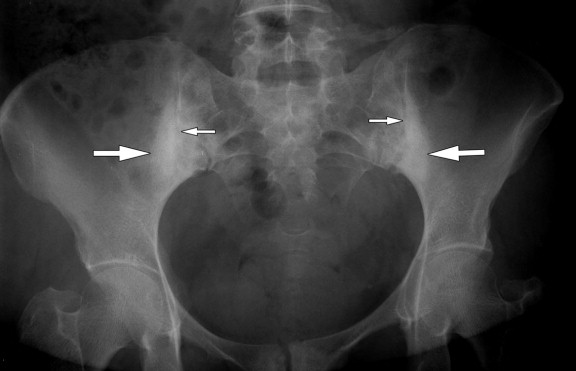

تشخیص این بیماری معمولاً بر اساس شرح حال بیمار، معاینه بالینی و آزمایشهای تصویربرداری انجام میشود. پزشک با بررسی حرکات مفصل و فشار بر ناحیه لگن میتواند به التهاب مشکوک شود.

رادیوگرافی، امآرآی و سیتیاسکن از روشهای متداول برای بررسی دقیق این مفصل هستند. گاهی نیز آزمایش خون برای بررسی عوامل التهابی یا عفونی انجام میشود. تشخیص درست، شرط لازم برای انتخاب بهترین روش درمانی است.